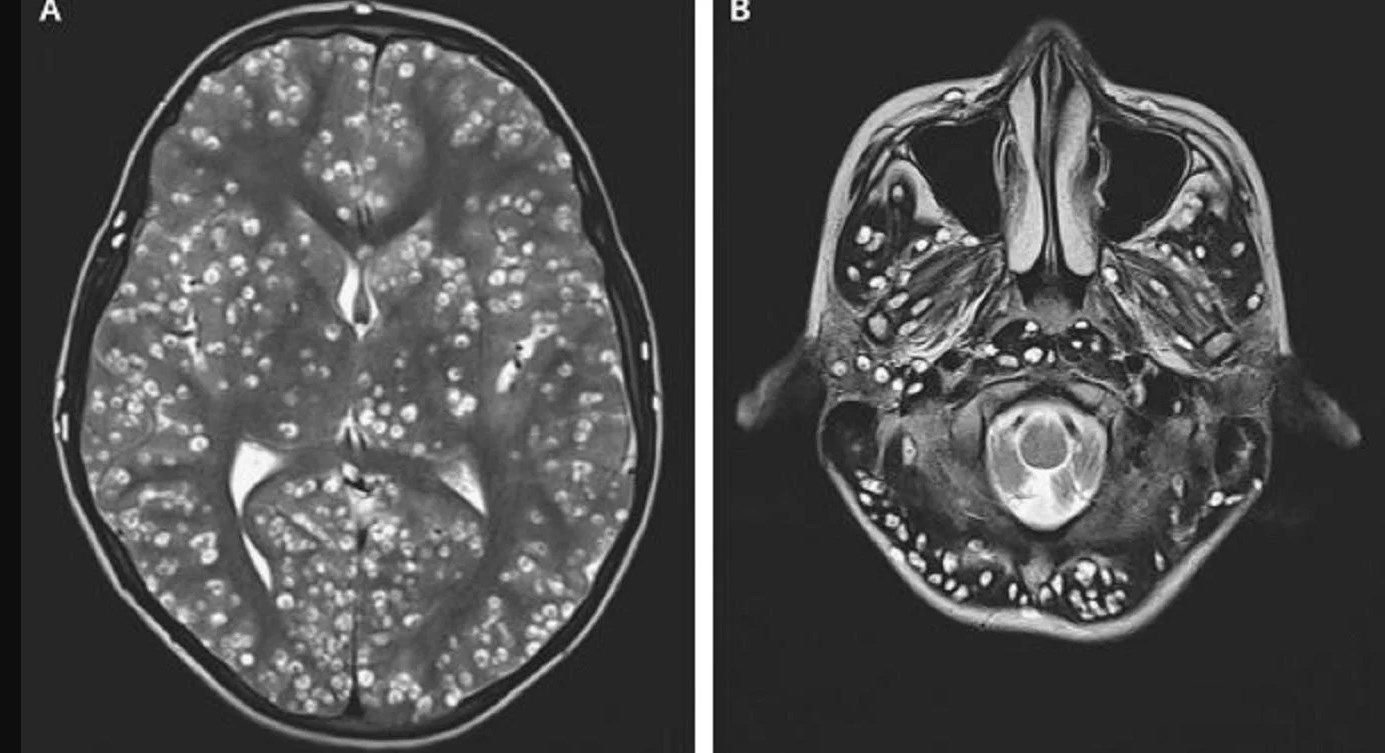

Para asombro de los profesionales, el estudio mostró que tanto las convulsiones como las lesiones en su cuerpo habían sido causadas por la presencia de quistes producidos por la Taenia Solium, un parásito que se transmite por la ingesta de carne de cerdo cruda o mal cocida.

A través de la producción de huevos, el gusano es capaz de esparcirse rápidamente por el organismo, generando quistes y dañando los tejidos, en una enfermedad conocida como cisticercosis. Lamentablemente, la cantidad de lesiones en el cerebro del adolescente era tan grande que los médicos no pudieron hacer nada para salvarle vida, y falleció luego de dos semanas bajo tratamiento con dexametasona y medicamentos antiepilépticos.